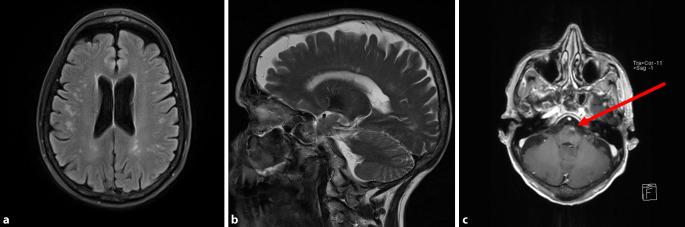

Eine 70-jährige Patientin stellte sich zur ätiologischen Abklärung einer MR-tomographischen Leukenzephalopathie vor (Abb. 1a). Klinisch-neurologisch bestanden eine leichtgradige Abduzensparese links sowie eine Feinmotorikstörung beider Hände und eine Gangunsicherheit seit etwa drei Jahren. Ein initiales MRT drei Jahre zuvor zeigte bihemisphärische, subkortikale Marklagerläsionen, die als vaskuläre mikroangiopathische Leukenzephalopathie gedeutet worden waren. Es fanden sich retrospektiv in der damaligen wie auch in der aktuellen MRT-Bildgebung kleine balkenassoziierte Läsionen. Der vor 2 Jahren erhobene Liquorstatus zeigte keine Pleozytose, ein erhöhtes Liquoreiweiß (610 mg/l) und identische oligoklonale Banden im Serum und Liquor. Wiederholte MR-tomographische Darstellungen der HWS und BWS erbrachten keine medullären Läsionen. In der TOF-Angiographie stellten sich die intrazerebralen Gefäße unauffällig dar. Die Patientin litt seit mehr als 25 Jahren an einer Colitis ulcerosa mit bei der aktuellen Vorstellung niedriger Krankheitsaktivität (Mayo-Score 1) unter Mesalazintherapie. Kardiovaskuläre Risikofaktoren wie eine arterielle Hypertonie, ein Diabetes mellitus oder ein Nikotinabusus lagen nicht vor. Eine konsiliarische augenärztliche Untersuchung ergab neben der Abduzensparese keine Auffälligkeiten. Hinweise für eine begleitende Arthritis fanden sich anamnestisch und in der Untersuchung nicht. Die Familienanamnese erbrachte keinen Hinweis auf eine hereditäre Genese. Laborchemisch detektierten wir einen mit 1:320 erhöhten ANA-Titer (Referenz <1:80) sowie positive Anti-Proteinase-3-(cANCA)-Antikörper (53,4 E/ml; Referenz <20 E/ml). Die erweiterte Labordiagnostik erbrachte keinen Hinweis auf eine infektiologische Ursache (HIV, Hepatitis, Lues, JC-Virus) oder eine Neurosarkoidose. Interleukin‑6 war nicht erhöht. Hinweise auf einen Vitaminmangel ergaben sich nicht. Liquordiagnostisch lagen aktuell erneut eine leichte Eiweißerhöhung (622 mg/l) sowie jetzt positive oligoklonale Banden Typ 2 im Liquor vor. Eine Liquorpleozytose fand sich nicht. In einer erneuten kranialen MR-Bildgebung zeigten sich supratentoriell unverändert zu 2018 die subkortikal im Marklager und im Balken gelegenen T2-Hyperintensitäten ohne Kontrastmittelaufnahme (Abb. 1a, b). Allerdings stellte sich neu eine flau kontrastmittelanreichernde Läsion im ventralen Pons links dar (Abb. 1c). Hinweise auf eine Granulomatose mit Polyangiitis (früher Wegener’sche Granulomatose) ergaben sich HNO-ärztlicherseits und im CT des Thorax nicht. Bei multifokalen, teils balkenassoziierten Läsionen sowie einer Konversion der oligoklonalen Banden seit 2017 war nun nach den erweiterten McDonalds-Kriterien die Diagnosestellung einer multiplen Sklerose (MS) möglich. Eine Erstmanifestation im höheren Lebensalter und bei langjähriger Colitis ulcerosa mit Nachweis von Proteinase-3-Antikörpern machte aber eine Assoziation mit der Colitis ulcerosa wahrscheinlicher. Wir führten eine probatorische Glukokortikoidstoßtherapie mit insgesamt 3 g Methylprednisolon über drei Tage durch, ohne dass eine Besserung der Abduzensparese im Verlauf von 2 Monaten resultierte. Wir empfahlen bei Vorliegen einer möglichen Assoziation zwischen einer chronisch-entzündlichen Darm- und möglichen entzündlichen ZNS-Erkrankung eine immunmodulatorische Off-label-Therapie mit dem Sphingosin-1-Phosphat-Rezeptor-Modulator Fingolimod, da andere Sphingosin-1-phosphat-Rezeptor-Modulatoren eine klinische Wirksamkeit bei der Colitis ulcerosa und MS gezeigt haben, aber noch nicht in Deutschland zugelassen sind. Der Beginn der immunmodulierenden Therapie wurde aber bei der Patientin bei klinischer Stabilität in Anbetracht der aktuellen COVID-19-Pandemie zunächst noch verschoben.